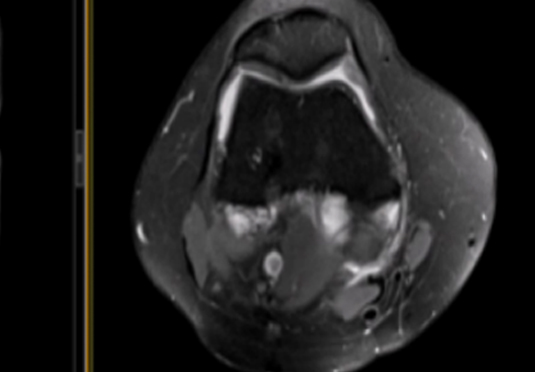

微創射頻消融術

適用于微創射頻熱消融術治療患者,引進權威醫療團體輔助引流。